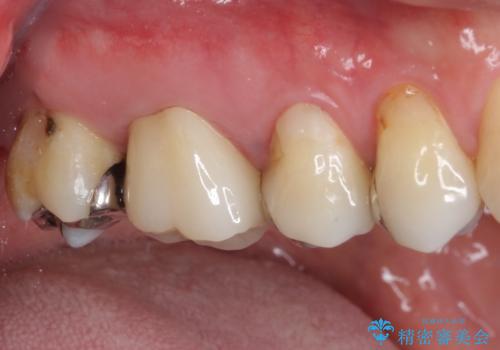

- 上の奥歯に咬んだときの痛みを感じて来院された患者様です。

まずは根管治療を行い、その後フルジルコニアクラウンにて補綴することとしました。